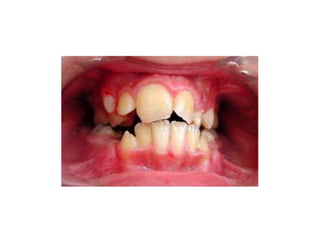

5. Transposition

Merupakan kondisi dimana dua gigi yang

bersebelahan berubah posisi pada dental arch.